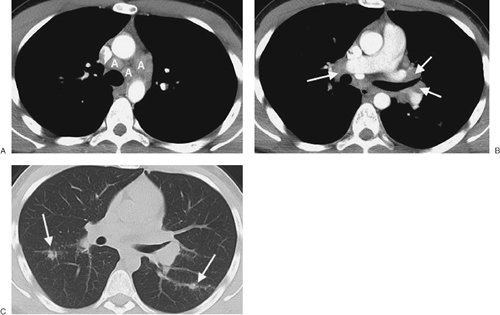

FIGURE 6-26. Sarcoidosis. A: CT scan of a 20-year-old man shows enlarged paratracheal and aortopulmonary lymph nodes (A). B: CT scan at a more inferior level shows bilateral hilar (arrows) lymphadenopathy. Enlargement of paratracheal and bilateral hilar lymph nodes is commonly seen with sarcoidosis and is referred to as the "1-2-3" sign or Garland triad. C: CT scan with lung windowing shows small, ill-defined nodules in a bronchovascular distribution (arrows); this is typical of the parenchymal findings seen with sarcoidosis.